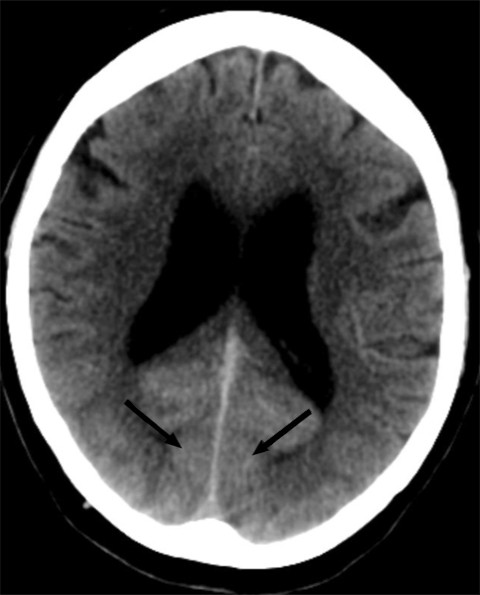

Thirty minutes after the acute onset of blindness, the patient underwent a brain CT and CT angiography of the cerebral arteries. The CT scan showed widespread diffuse contrast enhancement in bilateral (occipital) visual cortex, but no haemorrhage or infarction (Figure 1). CT angiography showed no vascular occlusion or vascular spasms. As expected with an intracranial dural arteriovenous fistula, dural veins showed increased visibility and filling with high-contrast arterialised blood.

The patient's CT scans showed contrast retention in bilateral visual cortex. As the CT had been performed without contrast, the visible contrast had to be from the conventional cerebral angiography performed two hours earlier. CT angiography showed open vessels, and there were no new lesions on the MRI. The clinical symptoms and imaging findings were thus inconsistent with cerebral ischaemia due to thromboembolism or vascular spasms.

Transient cortical blindness is a diagnosis of exclusion. A brain MRI and a CT scan of the head with CT angiography are indicated to rule out haemorrhagic or ischaemic causes of vision loss. MRI may be negative or may show hyperintensity on T2 and FLAIR sequences, as in vasogenic oedema. CT scans may be normal or may show contrast enhancement in occipital regions. CT angiography will show open vessels and no vascular spasms.